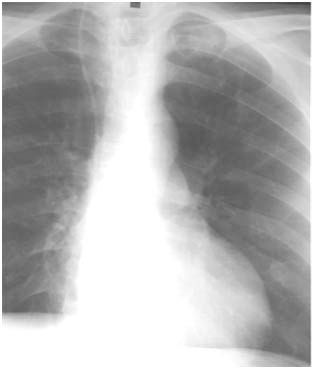

A 56-year-old man has been admitted on several prior occasions for left groin abcesses related to injection drug use. Comorbid disorders include diabetes and tobacco abuse. Recent test results for HIV and TB (PPD test) were negative. On past admissions related to intravenous abuse of heroin and cocaine, the patient was treated with antibiotics and incision with drainage. A CXR and subsequent CT scan, obtained for cough, revealed a left upper lobe nodule. Respiratory isolation was initiated on suspicion of TB.

Figure 1

Figure 2- Left upper lobe nodule 2.2cm by 1.9cm